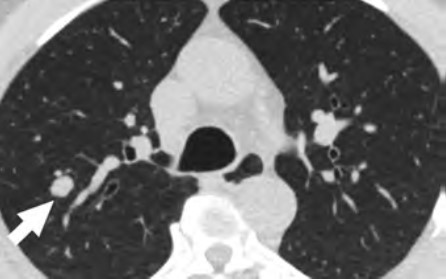

At the individual level, barriers to participation include conflicting personal and health schedules, such as medical appointment times that conflict with working hours, dependent care schedules, understanding the importance of adherence to annual LCS and recommended follow-up (Fig. 4) for the detection of early LC, anxiety and stigma about LC diagnosis, concerns about radiation exposure, and access to primary care services to get LCS referrals [4, 9, 10, 26].